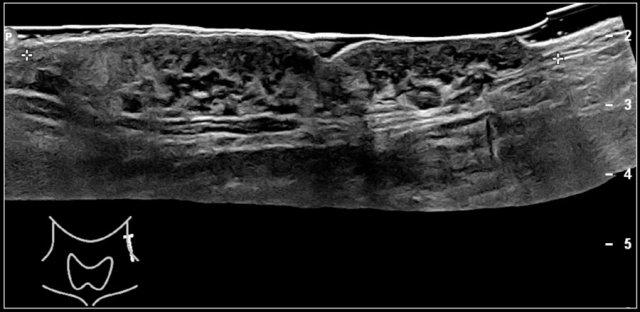

Hashimoto’s thyroiditis: An enlarged thyroid gland with a diffuse inhomogeneous structure and hyperemia is seen in a ten-year-old girl

Các dạng viêm tuyến giáp phổ biến nhất là viêm tuyến giáp Hashimoto và bệnh Graves.

Cả viêm tuyến giáp Hashimoto và bệnh Graves đều có thể biểu hiện là tuyến giáp to và tăng sinh mạch máu.

Trên siêu âm, tuyến giáp to lan tỏa và không đồng nhất.

Trên siêu âm Doppler màu, lưu lượng máu thường bình thường nhưng có thể tăng như trong bệnh Graves.

Trong bệnh Graves, tuyến giáp cũng to ra và cho thấy sự tăng tưới máu.

Trên siêu âm Doppler màu, hình ảnh này được mô tả như một địa ngục lửa với màu đỏ và xanh.

Đây là hình ảnh của một bé gái 16 tuổi mắc cường giáp.

Tuyến giáp to lan tỏa với tình trạng sung huyết.

Chẩn đoán cuối cùng là bệnh Graves.